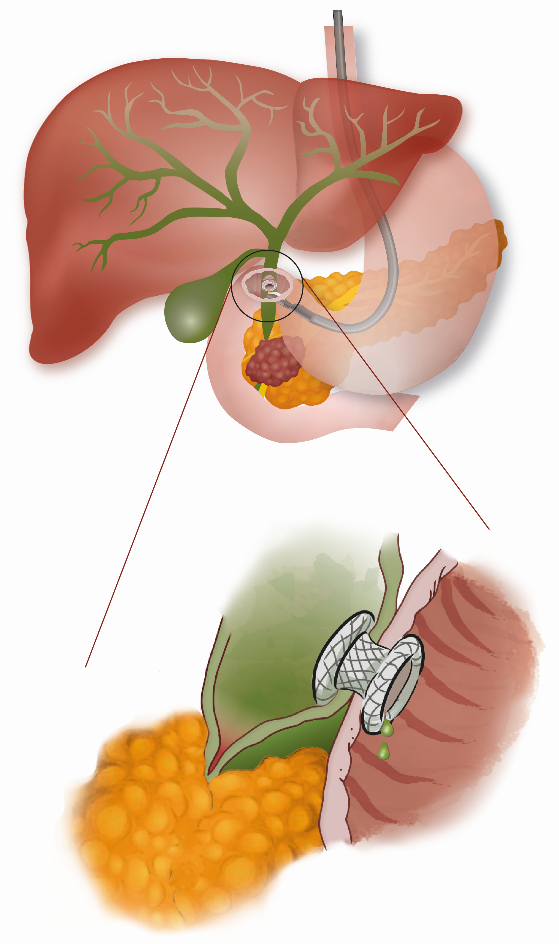

Bij een ERCP wordt de uitgang van de galweg opgezocht en wordt er een buisje geplaatst door de tumor om zo de vernauwing van de galweg te verwijden (figuur 1).

Figuur 1. ERCP